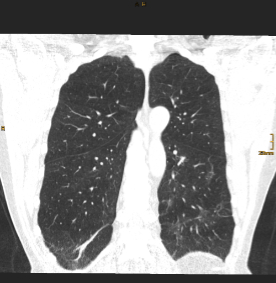

Pressebilder frei zum Download: ©Univ.-Klinik für Radiologie Innsbruck

BU: CT Thorax eines Teilnehmers während des stationären Aufenthalts (Bild links) und nach einem Jahr (Bild rechts) im Vergleich. Die initial ausgeprägten Gewebsvermehrungen sind deutlich rückläufig, jedoch zeigen sich residuell noch feine lineare Verdichtungen in beiden Unterlappen.